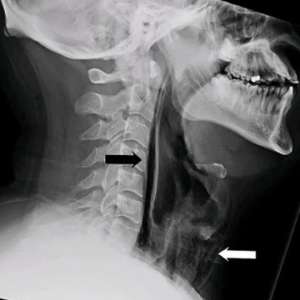

Мужчина столкнулся с разрывом горла, когда попытался подавить чих.

В попытке сдержать чих он почувствовал «хлопок» в шее, за которым последовали боль и трудности при глотании. МРТ показало, что воздух выходил через разрыв из трахеи в мягкие ткани шеи. В течение следующих нескольких дней мужчину кормили через зонд, чтобы дать тканям время для заживления.

Когда мы прикрываем нос и рот во время чихания, воздуху некуда деваться, и его давление разрывает мягкие ткани, нанося им вред.